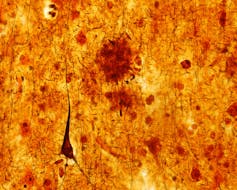

The deposition of amyloid βpeptide (Aβ) in amyloid plaques is one of the histopathological hallmark lesions of Alzheimer’s disease (AD) together with neurofibrillary tangles (NFTs) Neuritic plaques represent a subset of the Aβ plaques characterized by the presence of dystrophic neurites in the plaques that can be stained with antibodies against abnormal τprotein 11, 18, 35, 51, 70. In Alzheimer's disease, the fragments accumulate to form hard, insoluble plaques plaques between nerve cells (neurons) in the brain Amyloid is a general term for protein fragments that the body produces normally Beta amyloid is a fragment of a protein snipped from another protein called amyloid precursor protein (APP). Learn what Alzheimer’s disease does to the brain, including plaque formation, cell death, lost connections, and brain inflammation and shrinkage.

Diabetes increases neuritic damage around amyloid plaques in Alzheimer's disease University of Eastern Finland Research News Share Print EMail New research from the University of Eastern. Amyloid Plaques One of the hallmarks of Alzheimer's disease is the accumulation of amyloid plaques between nerve cells (neurons) in the brain Amyloid is a general term for protein fragments that the body produces normally Beta amyloid is a fragment of a protein snipped from another protein called amyloid precursor protein (APP). Amyloid plaques are extracellular deposits of the amyloid beta protein mainly in the grey matter of the brain Degenerative neuronal elements and an abundance of microglia and astrocytes can be associated with amyloid plaques Some plaques occur in the brain as a result of senescence, but large numbers of plaques and neurofibrillary tangles are characteristic features of Alzheimer's disease Abnormal neurites in amyloid plaques are tortuous, often swollen axons and dendrites The neurites contai.

Alzheimer's disease has been identified as a protein misfolding disease (proteopathy), caused by plaque accumulation of abnormally folded amyloid beta protein and tau protein in the brain Plaques are made up of small peptides , 39–43 amino acids in length, called amyloid beta (A β ). Alzheimer's disease is a neurodegenerative condition that is characterized by the buildup of clumps of betaamyloid protein in the brain Exactly what causes these clumps, known as plaques, and. Aβ is the focus in the fight against Alzheimer's disease A central approach in the search for a cure is dissolving the plaques in the patients' brains "Early diagnosis of Alzheimer's disease is crucial to prevent Aβ from causing irreparable damage in the brain," says Dominik Röhr Promising medications are currently undergoing approval.

Senile plaque is one of the most prominent pathological hallmarks of Alzheimer’s disease (AD) However, the mechanism governing the generation of senile plaques remains a mystery Many researchers believed that senile plaques are derived from neuronal cells, however, there is also strong evidence showing that senile plaques are linked with cerebral microhemorrhage. Senile plaque is one of the most prominent pathological hallmarks of Alzheimer’s disease (AD) However, the mechanism governing the generation of senile plaques remains a mystery Many researchers believed that senile plaques are derived from neuronal cells, however, there is also strong evidence showing that senile plaques are linked with cerebral microhemorrhage. Amyloid Plaques and Tau Tangles are believed to be the two molecules responsible for the brain damage associated with Alzheimer's disease Both Plaques and Tangles are present in the brains of individuals without Alzheimer's;.